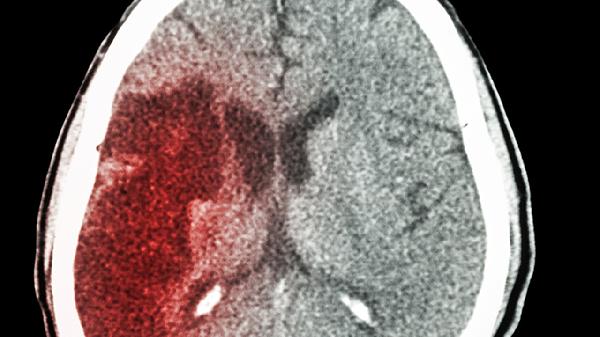

脑出血病人吃什么好 这样调理更有益健康

脑出血病人的饮食需遵循低盐、低脂、高纤维原则,每日食盐摄入不超过5克,烹调油控制在25克以内。恢复期可在康复师指导下进行肢体功能训练,如床上被动活动、坐位平衡练习等。保持每日饮水量1500-2000毫升,养成定时排便习惯。定期复查头颅CT监测血肿吸收情况,出现头痛加重、意识模糊等异常症状需立即就医。